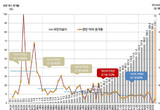

코로나19 이달까지 유행 지속 예상

- 2025-09-05 17:14

- 황재연 기자